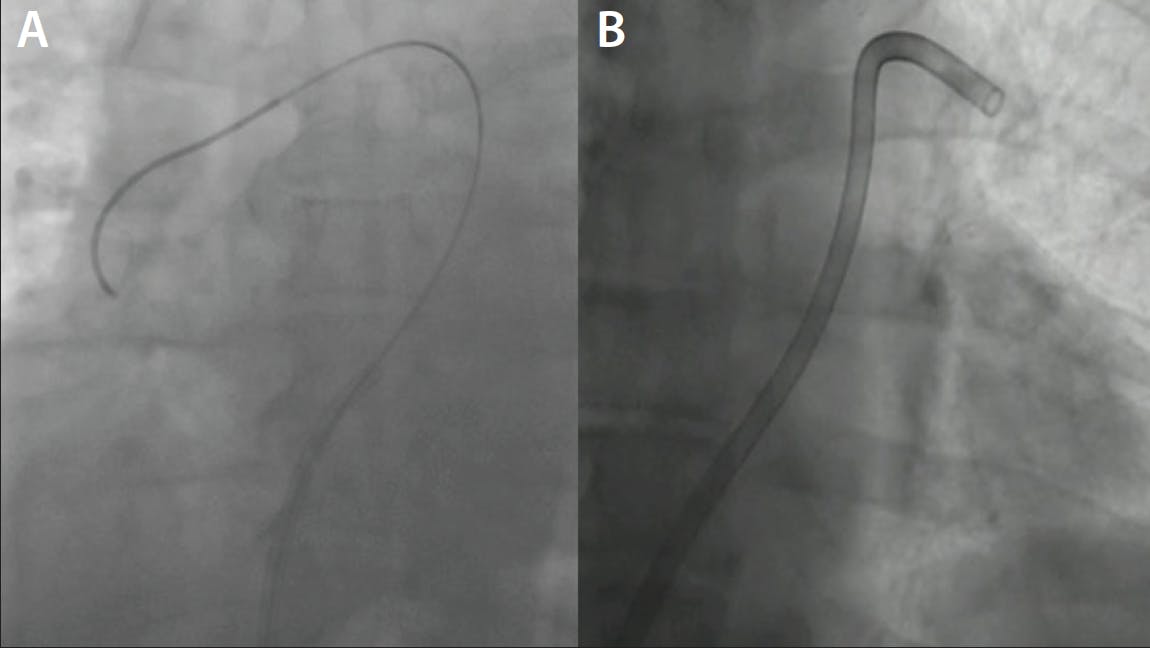

A man in his late 50s with no cardiac history and who was a former smoker presented to our department for acute chest pain, with symptom onset 2 hours prior. The pain was typical and an electrocardiogram showed an anterior ST-segment elevation myocardial infarction (STEMI), so he was immediately taken to the cath lab. A coronary angiogram showed complete left anteriror descendant (LAD) coronary occlusion in the medial part (Figure 1) with TIMI flow 0. After coronary wiring and a soft predilation, we appreciated a great thrombotic burden occupying almost one-third of the vessel (Figure 2).

Figure 1. Angiographic view (caudal 35°) showing complete LAD occlusion in the medial part.

Figure 2. Angiographic view (cranial 40°) showing incomplete flow restoration with high thrombus burden in the LAD after wiring passage and soft predilation.

TREATMENT OPTIONS AND COURSE OF TREATMENT

Due to the high thrombus burden, it was determined that balloon angioplasty or direct stenting could lead to distal thrombus migration. This could result in slow flow/no-reflow phenomenon with hemodynamic repercussions due to the vessel-wide myocardial perfusion territory. Performing manual thrombus aspiration with this large thrombus formation could potentially have been ineffective and time consuming, and time is muscle in myocardial infarction. As we know from the European Society of Cardiology 2023 guidelines on management of acute coronary syndrome,1 routine thrombus aspiration is not recommended, but in cases of large residual thrombus burden after opening the vessel with a guidewire or a balloon, thrombus aspiration may be considered. The class of indication is driven mainly by the risk of stroke observed in manual aspiration trials.2,3 We decided to try to remove the thrombus with the Penumbra Indigo System CAT-RX, due to its encouraging data on safety and efficacy and low risk of ischemic stroke.4,5

INTERVENTION

Three CAT RX passes were performed from proximal to distal, with aspiration continuously on as the catheter was advanced in a slow, controlled manner. Angiography after CAT RX showed an optimal thrombus resolution and lesion visualization. A stent was then placed, resulting in final TIMI III flow with preservation of all side branches (Figure 3). At the end of the procedure, we retrieved a massive 3.5-cm-long thrombus from the Penumbra canister (Figure 4).

Figure 3. Angiographic view (cranial 40°) showing final TIMI III flow after CAT-RX and stenting in the LAD.